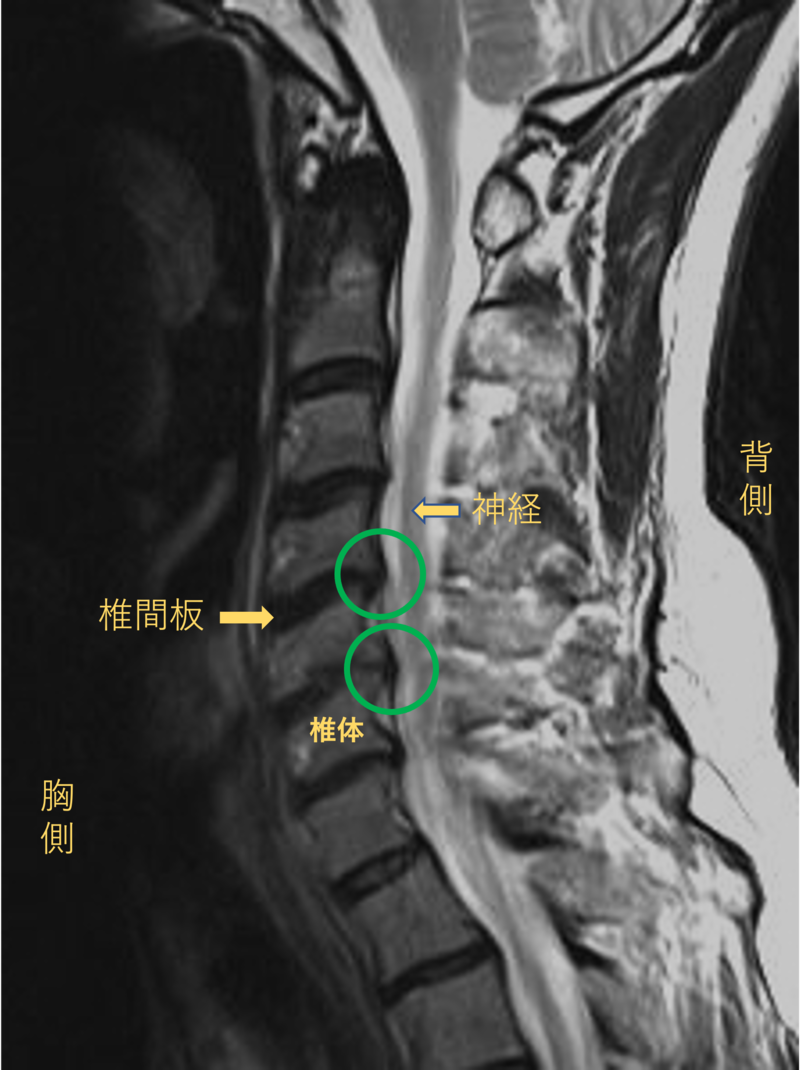

首を横から見たMRI画像です。

頚椎という骨と骨の間に椎間板と呼ばれるクッションがあります。

このクッションの中身が飛び出す状態が椎間板ヘルニアと呼ばれます。

このMRI画像では、椎間板が背中側に飛び出して神経が圧迫されることが痛みの原因となっておりました。